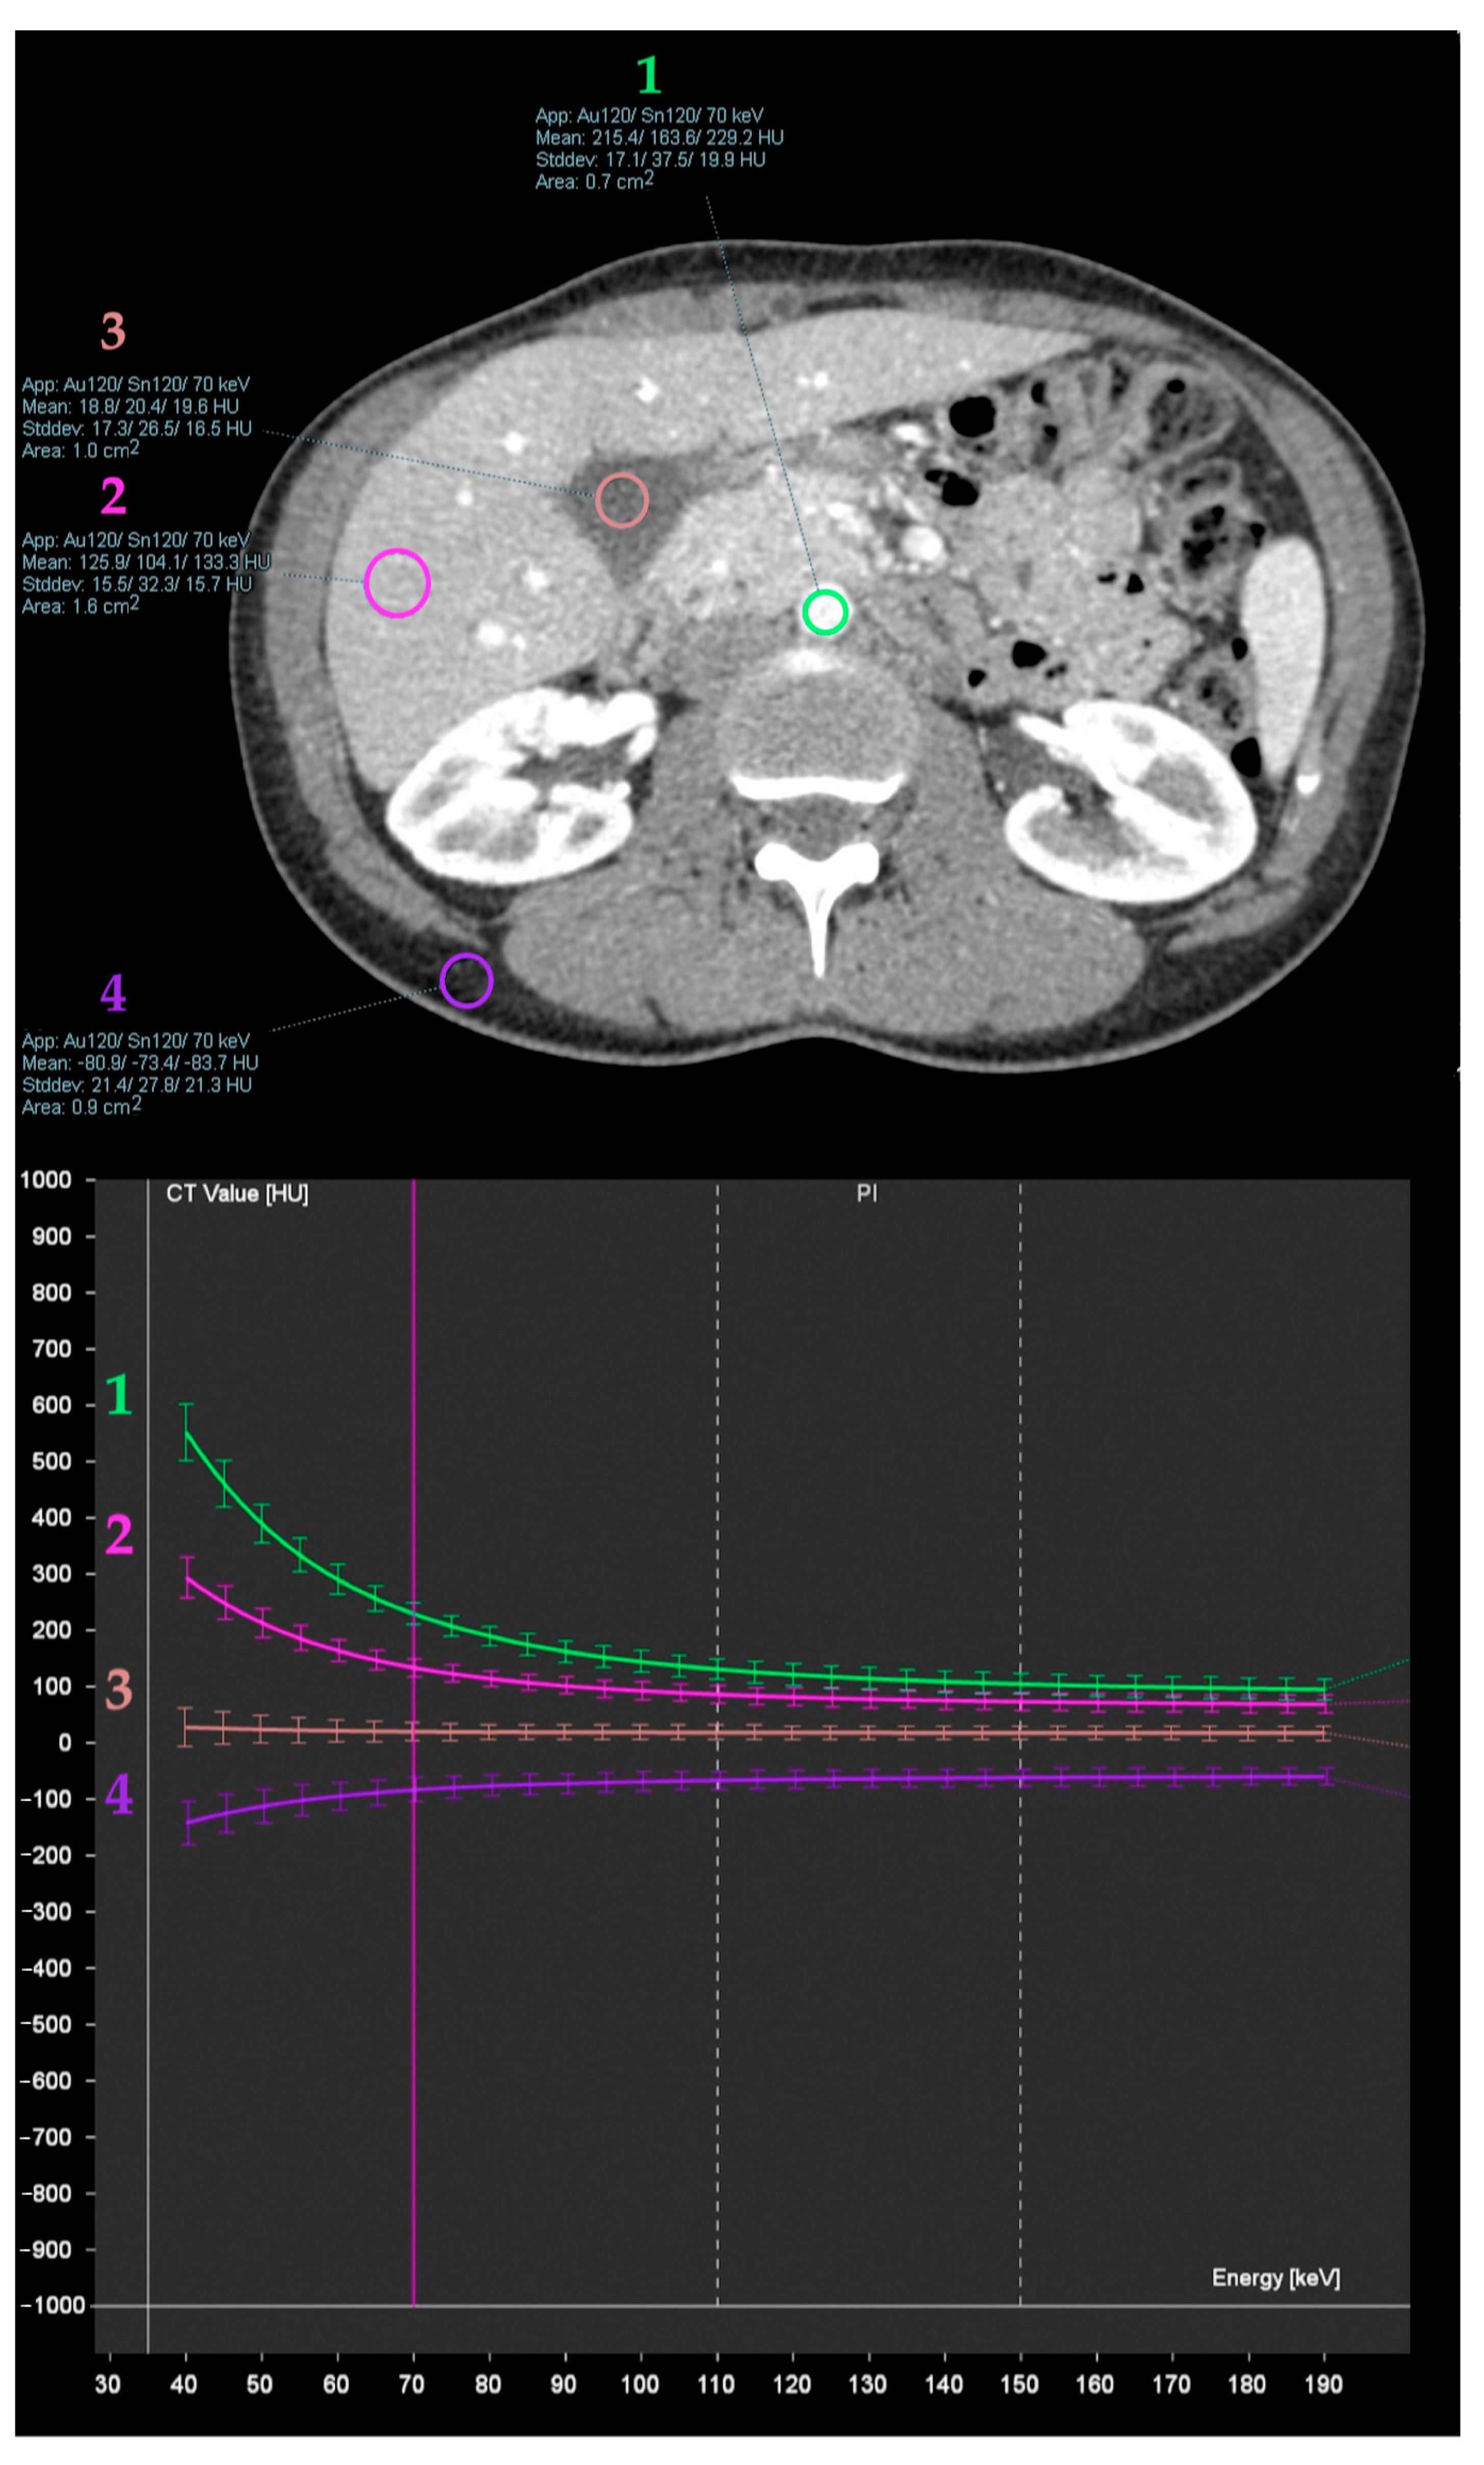

- Wang, Q.; Shi, G.; Qi, X.; Fan, X.; Wang, L. Quantitative analysis of the dual-energy CT virtual spectral curve for focal liver lesions characterization. Eur. J. Radiol. 2014, 83, 1759–1764. [Google Scholar] [CrossRef]